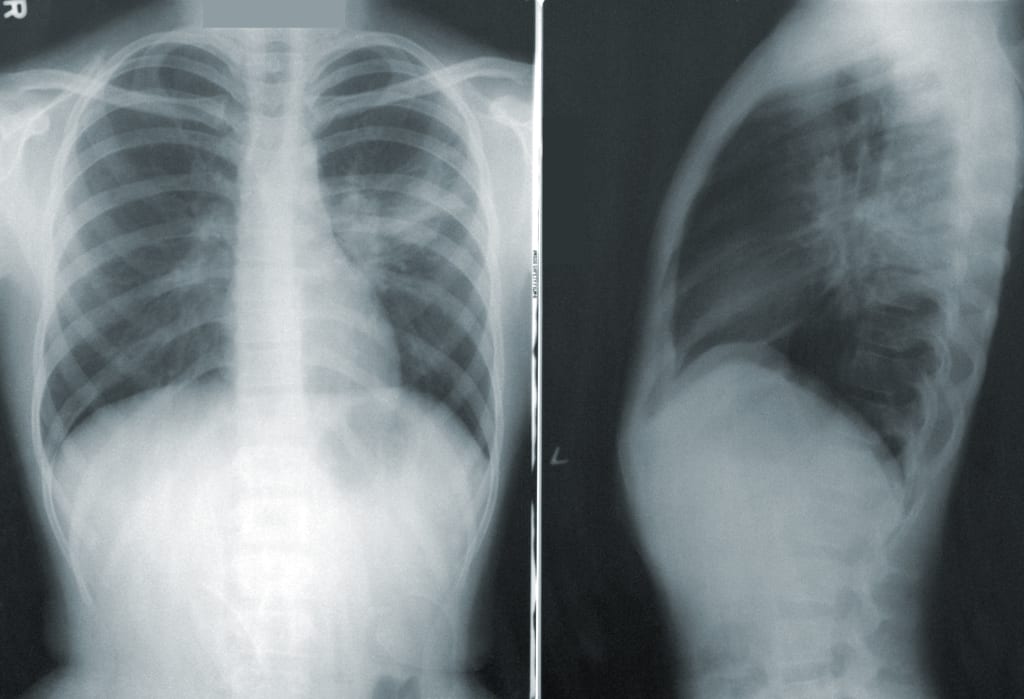

Children are being affected by a mysterious condition known as 'white lung pneumonia'. Here is the essential information you should be aware of.

In China, similar cases on a larger scale have been observed, where respiratory illnesses like influenza, rhinoviruses, and mycoplasma pneumonia, also known as white lung syndrome, are circulating in communities.